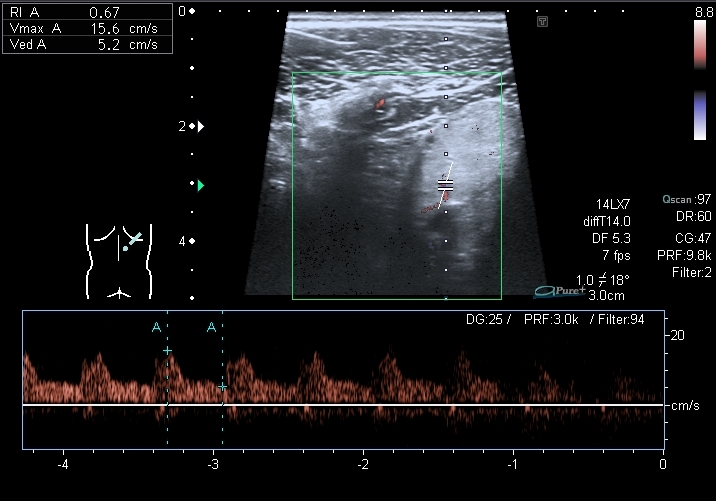

Спектрограммы кровотока в правой и левой почках:

I20121224144609218.jpg

I20121224144609296.jpg